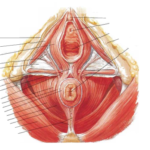

Sin embargo, el suelo pélvico no se compone únicamente de la musculatura.

La mayor parte del suelo pélvico incluye también tejido conjuntivo, entre ellos ligamentos, tendones y fascias, que proporcionan estabilidad, elasticidad y soporte.

La interacción entre estos tejidos y los músculos permite que el suelo pélvico realice funciones esenciales como el control de esfínteres, el sostén de órganos, la estabilidad del tronco y la participación en la vida sexual.

Fuente: Netter. Atlas de anatomía humana